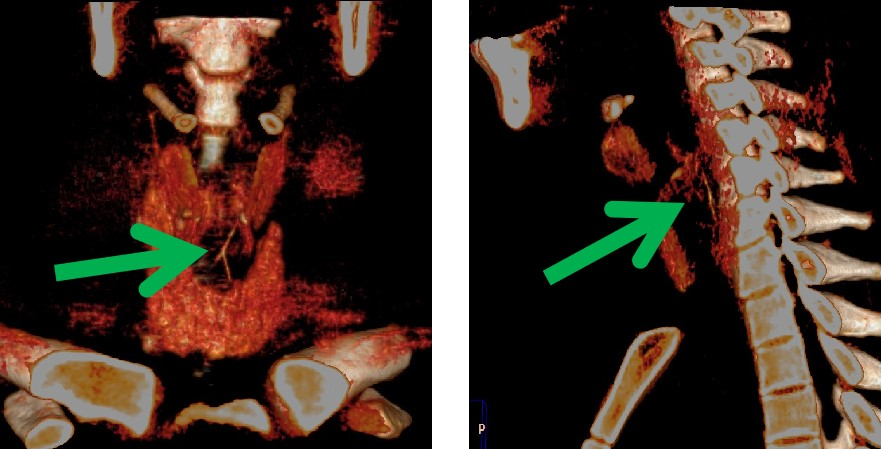

近日,我科来了一位十九岁的患者,一小时前吃鱼,一个不小心,把鱼刺咽下去了。感觉咽部不适异物感,急忙来医院就诊。先进行了喉镜检查 ,没有发现鱼刺的踪影。便连忙来到我科,进行食管异物CT扫描。此时,我科医生的火眼金睛该登场了,果然一下子就发现了罪魁祸首——狡猾的鱼刺。在患者的颈6椎体平面食道内,我们看到一个倒“Y”形的高密度影。我科医生又通过计算机后处理技术,很快这根鱼刺既直观又立体的展现在我们的眼前,鱼刺你终于藏不住了吧!

CT薄层重建图像结合后处理技术能多平面、多方位观察及定位,了解异物与食管壁、周围组织间的关系与损伤程度,主要重建方法包括多平面重建 (multiplanar reconstruction,MPR)、最大密度投影 (maximum intensity projection,MIP) 及容积再现 (volume rendering,VR)。

MPR、VR 及 MIP 多种重建方式的联合应用可对食管异物及早诊断,确定异物大小、形态、走向及位置,能多角度、任意方位地对组织器官进行观察和分析,直观、立体显示异物与周围组织结构的关系及有无并发症,为临床治疗方案的选择提供较大的指导意义,是诊断食管异物的可靠方法,已经成为食管异物诊断的首选检查方法。